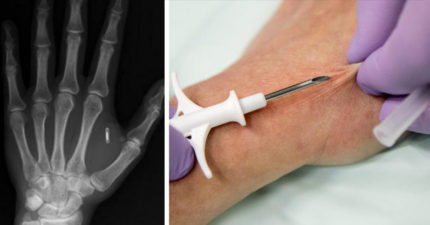

瑞典公司在員工「皮下植入晶片」,剝奪人權?員工:「超方便、超喜歡!」(影片)